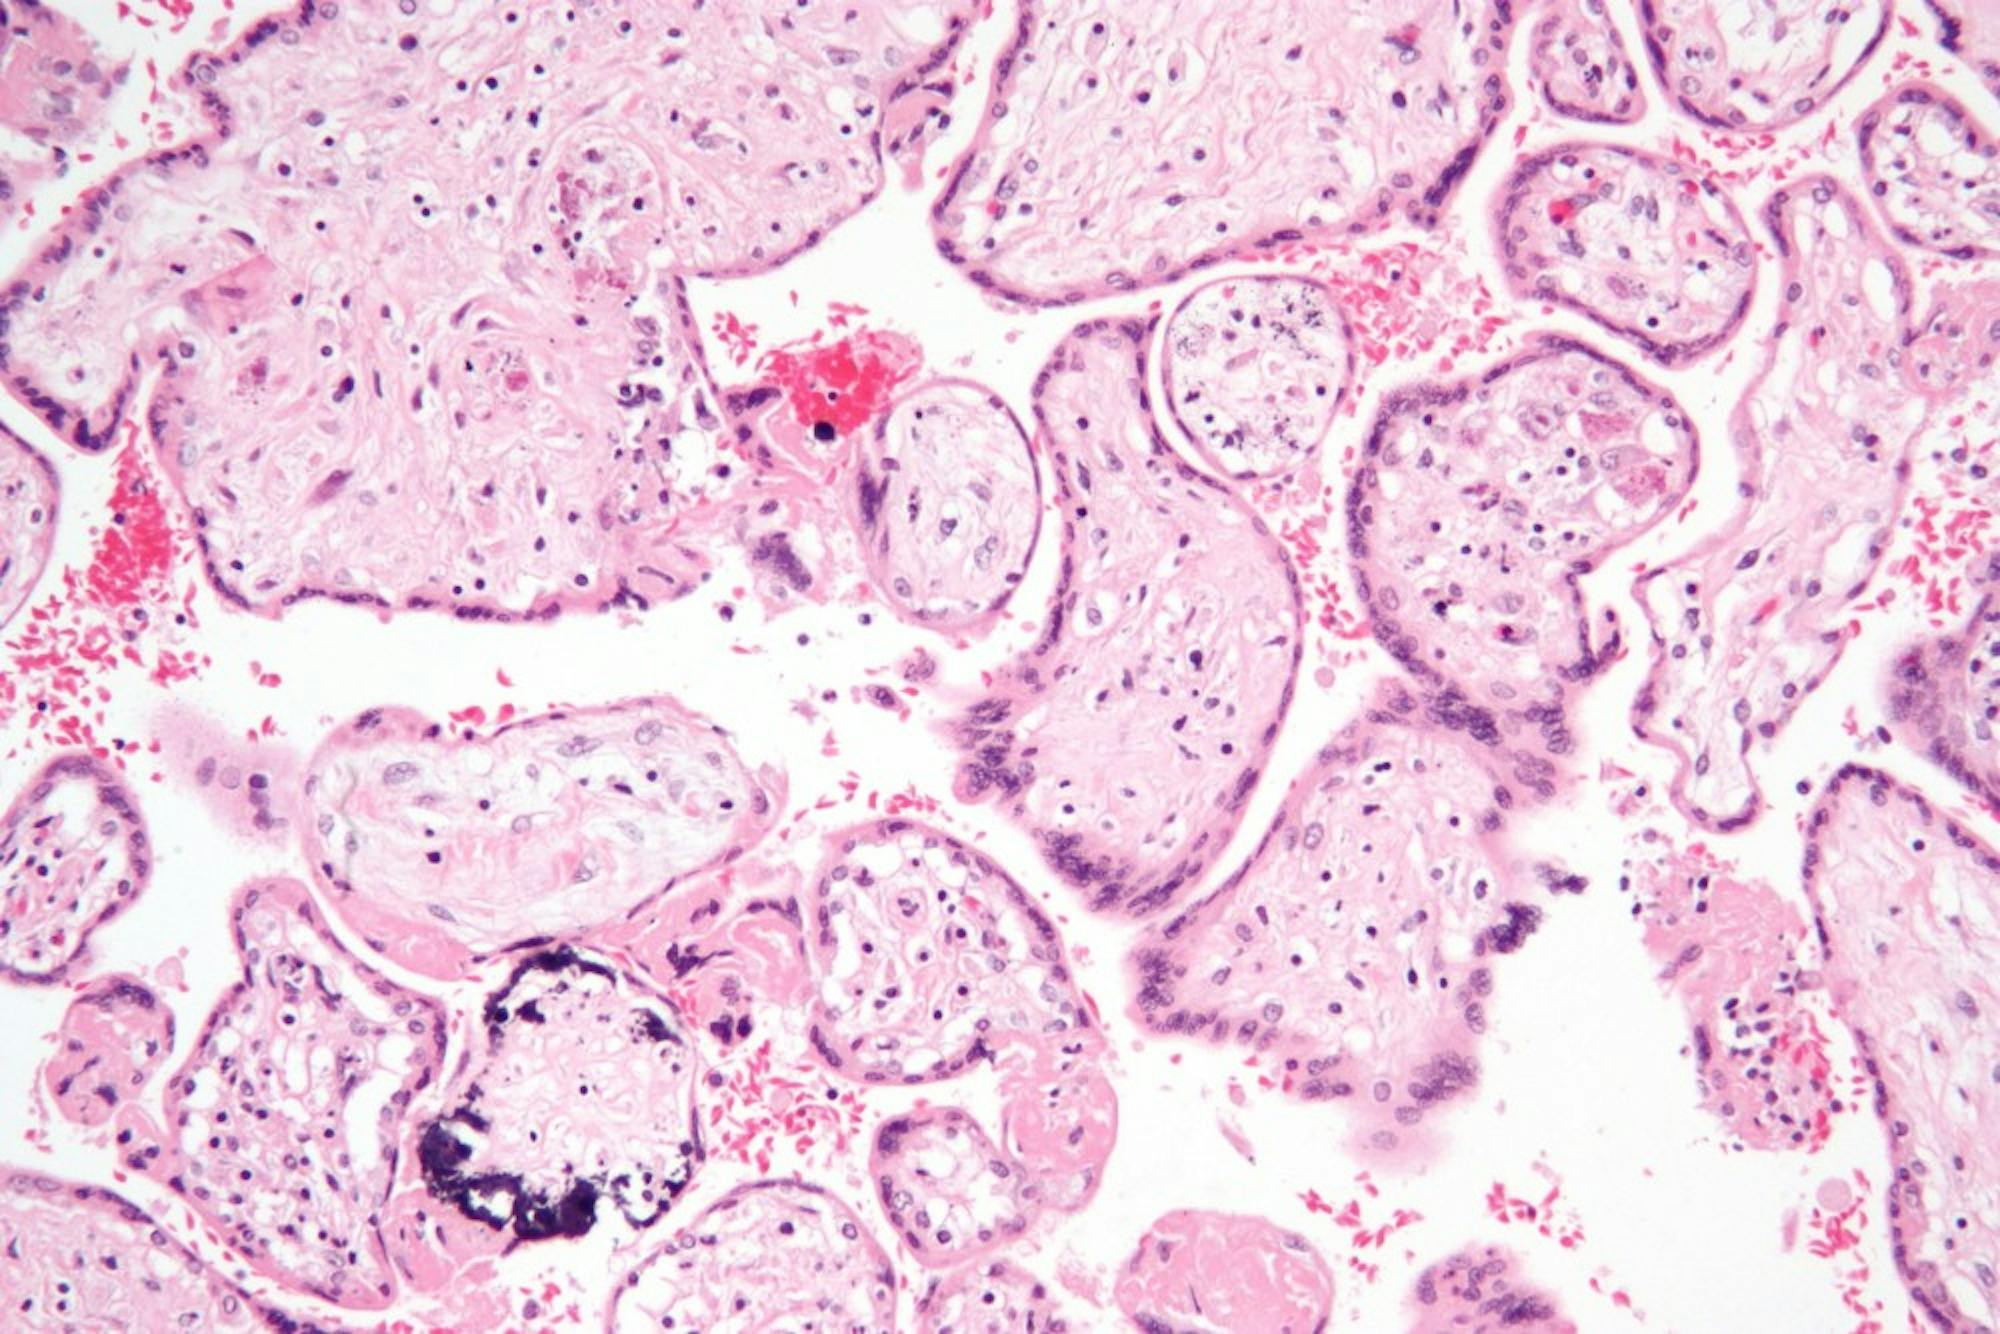

Human cytomegalovirus

Human cytomegalovirus, seen here, is a herpes family virus.